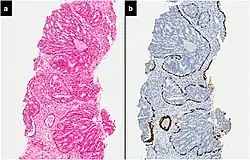

Intraductal carcinoma

Intraductal carcinoma of the prostate gland (IDCP), which is now categorised as a distinct entity by WHO 2016, includes two biologically distinct diseases. IDCP associated with invasive carcinoma (IDCP-inv) generally represents a growth pattern of invasive prostatic adenocarcinoma while the rarely encountered pure IDCP is a precursor of prostate cancer.[20] The diagnostic criterion of nuclear size at least 6 times normal is ambiguous as size could refer to either nuclear area or diameter. If area, then this criterion could be re-defined as nuclear diameter at least three times normal as it is difficult to visually compare area of nuclei.[20] It is also unclear whether IDCP could also include tumors with ductal morphology.[20] There is no consensus whether pure IDCP in needle biopsies should be managed with re-biopsy or radical therapy. A pragmatic approach would be to recommend radical therapy only for extensive pure IDCP that is morphologically unequivocal for high-grade prostate cancer.[20] Active surveillance is not appropriate when low-grade invasive cancer is associated with IDCP, as such patients usually have unsampled high-grade prostatic adenocarcinoma.[20] It is generally recommended that IDCP component of IDCP-inv should be included in tumor extent but not grade.[20] However, there are good arguments in favor of grading IDCP associated with invasive cancer.[20] WHO 2016 recommends that IDCP should not be graded, but it is unclear whether this applies to both pure IDCP and IDCP-inv.[20]

-

![Intraductal carcinoma of the prostate with an infiltrative growth pattern may be morphologically difficult to distinguish from invasive cancer. One focus shows comedonecrosis (arrow), morphologically suggesting Gleason pattern 5 invasive carcinoma (a haematoxylin and eosin, b CK5/6)[20]](./_assets_/Micrograph_of_intraductal_carcinoma_of_the_prostate_with_an_infiltrative_growth_pattern%252C_with_comedonecrosis.jpg) Intraductal carcinoma of the prostate with an infiltrative growth pattern may be morphologically difficult to distinguish from invasive cancer. One focus shows comedonecrosis (arrow), morphologically suggesting Gleason pattern 5 invasive carcinoma (a haematoxylin and eosin, b CK5/6)[20]

Intraductal carcinoma of the prostate with an infiltrative growth pattern may be morphologically difficult to distinguish from invasive cancer. One focus shows comedonecrosis (arrow), morphologically suggesting Gleason pattern 5 invasive carcinoma (a haematoxylin and eosin, b CK5/6)[20] -

![Intraductal carcinoma of the prostate with very patchy basal cells identified by immunohistochemistry. At least some of the glands lacking basal cell immunoreactivity represent intraductal rather than invasive carcinoma (a haematoxylin and eosin, b CK 5/6)[20]](./_assets_/Micrograph_of_intraductal_carcinoma_of_the_prostate_with_very_patchy_basal_cells.jpg) Intraductal carcinoma of the prostate with very patchy basal cells identified by immunohistochemistry. At least some of the glands lacking basal cell immunoreactivity represent intraductal rather than invasive carcinoma (a haematoxylin and eosin, b CK 5/6)[20]

Intraductal carcinoma of the prostate with very patchy basal cells identified by immunohistochemistry. At least some of the glands lacking basal cell immunoreactivity represent intraductal rather than invasive carcinoma (a haematoxylin and eosin, b CK 5/6)[20]